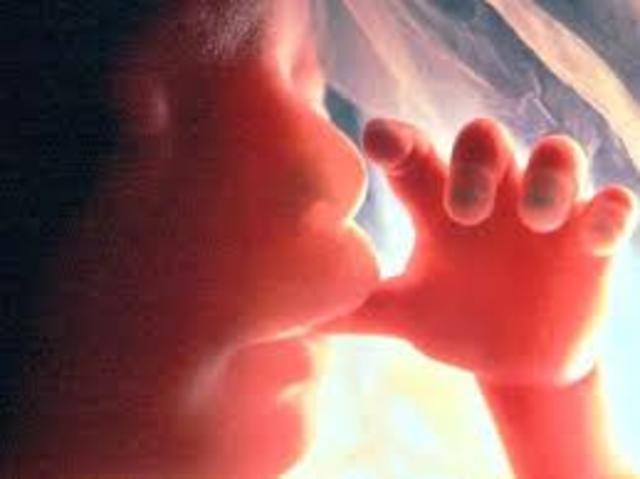

• during the end of the fetus period

during the end of the fetus period

week 9 to birth, the fetus continuous to grow, legs,head,fingers etc. At 10 weeks it starts to swallow and kick. Week 11 its almost fully formed. Week 12 baby starts to open and close its fingers. Mouth will start sucking movements. Intestine will move into abdomen cavity. Week 13 first trimester ends finger prints star to form. It is almost 3 inches long.